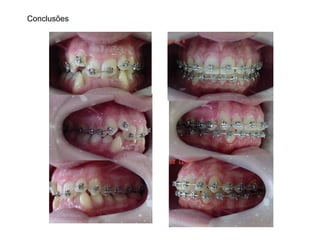

Conclusões

Elementos de Diagnóstico PerfilMole Facial Convexo | Padrão Vertical | Nariz Proeminente Assimetria Discreta | Linha do Sorriso Adequada Classe I | Overbite | Mordida Cruzada Post-direita | Mordida Aberta 12/43 DM = - 10,2 mm Spee = -3 mm DC = - 1,6 mm IMPA 88° 18a 3m Planejamento XP 18, 28, 38 e 48 Aparelhos Fixos Autoligantes Passivos “Damon High” slot .022” 1)N/A (arcos red. NiTi TA) 2)2 mm de Desgastes interproximais 33 a 43 3)Arcos ret. Niti 4)Intercuspidação 5)Finalização (arcos ret. Aço inox.) 6)Remoção e Contenções